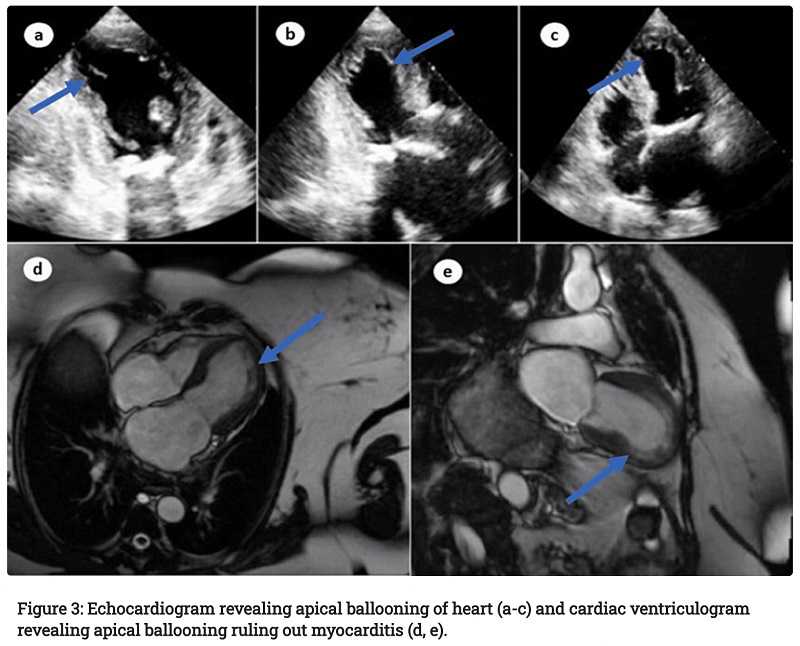

Tests op covid-19 bleven negatief. Een ECG en transthoracale echocardiografie toonden duidelijke afwijkingen in de hartfunctie, en de artsen vonden ook longoedeem op de röntgenfoto. De patiënte leed aan aanhoudende tachycardie en bloeddrukschommelingen. In de loop van de ziekte raakte ze in shock. Een longembolie en trombotische of obstructieve laesies in de kransslagaders konden worden uitgesloten, maar een MRI liet een duidelijke ballonvorming van het hart zien, maar geen myocarditis. Op basis hiervan en van de eerdere coronavaccinatie stelden de artsen de diagnose TCM – er kon geen andere oorzaak voor de ernstige hartklachten gevonden worden.